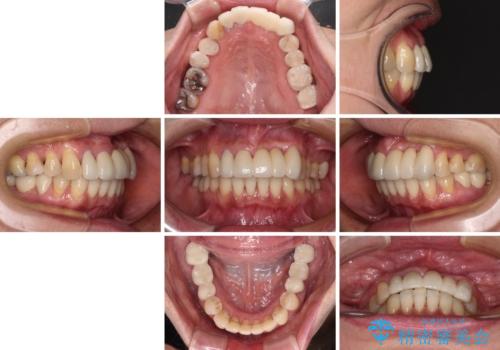

前歯は抜歯が必要であったので、抜歯を行い、その後歯肉移植をおこなった上でオールセラミックブリッジによる補綴治療を行うこととしました。

下顎と上顎臼歯部については矯正治療を行い、奥歯の欠損部位はオールセラミックブリッジを、その他の銀歯はセラミックインレーなどにより治療を行うこととしました。

気になっている部分を全て治療したことで、費用はかかりましたが、仕上がりには大変満足していただき、治療をおこなって良かったと仰っていただきました。